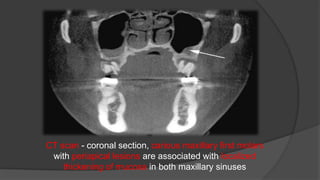

CT scan - coronal section, carious maxillary first molars

with periapical lesions are associated with localized

thickening of mucosa in both maxillary sinuses